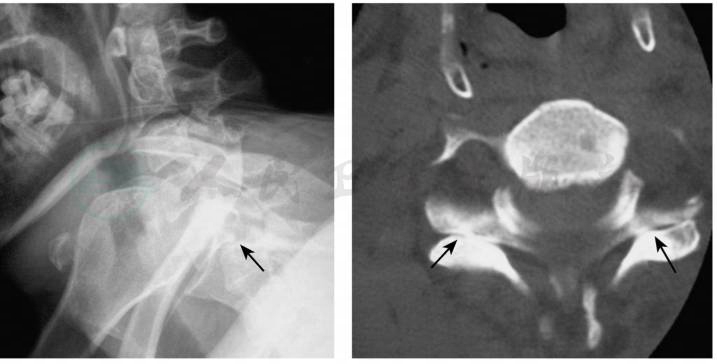

图1X线及CT显示C5~6双侧小关节脱位

X线侧位片上损伤节段椎体前移的距离至少是椎体前后径的1/2,上位椎体的下关节突位于下位椎体上关节突的顶部或前方,棘突间的距离加大。正位片上钩椎关节关系紊乱,小关节相互关系显示不清。CT可显示典型的双侧小关节脱位征,CT和MRI还有助于鉴别双侧还是单侧脱位。